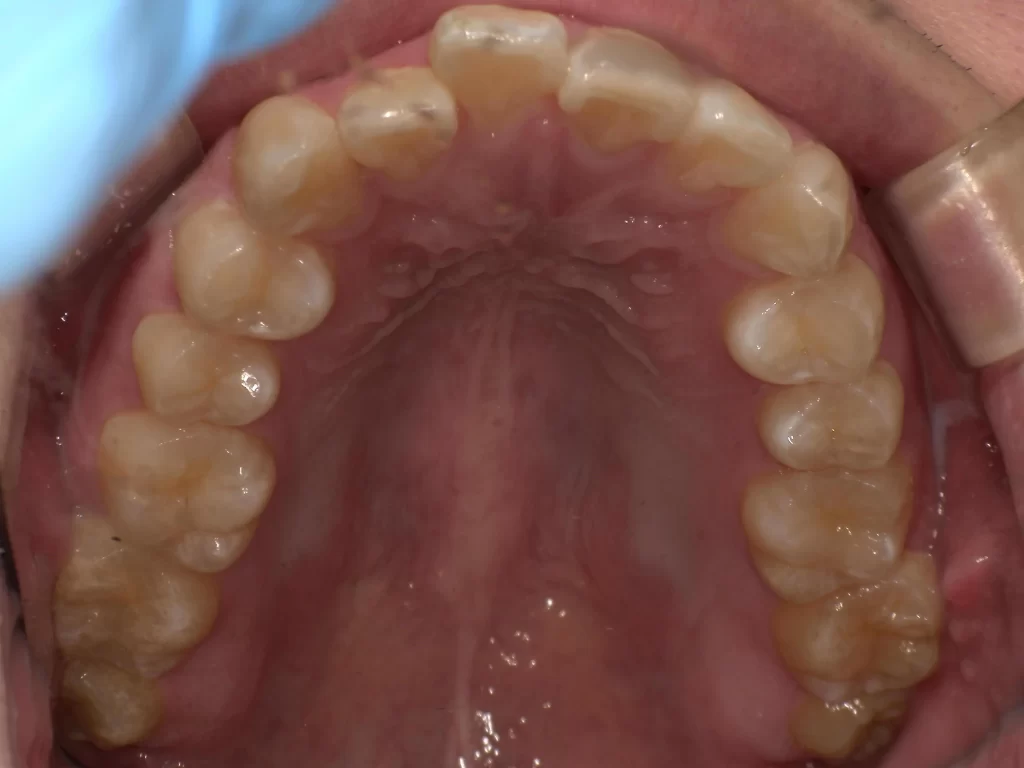

症例⑤:10歳・ガタガタ・出っ歯・深い噛み合わせ

【使用期間:3ヶ月】

歯が生えるスペースが足りずガタガタしており、噛み合わせも深い状態でした。

▼ 治療前(Before)

▼ 使用3ヶ月後(After)

- 年齢・症状: 10歳、叢生(ガタガタ)、過蓋咬合

- 治療法: プレオルソ

- 期間: 3ヶ月

- 結果: 装置を使うことで歯列の横幅が拡大し、ガタつきが自然に改善されました。深い噛み合わせも良くなっています。